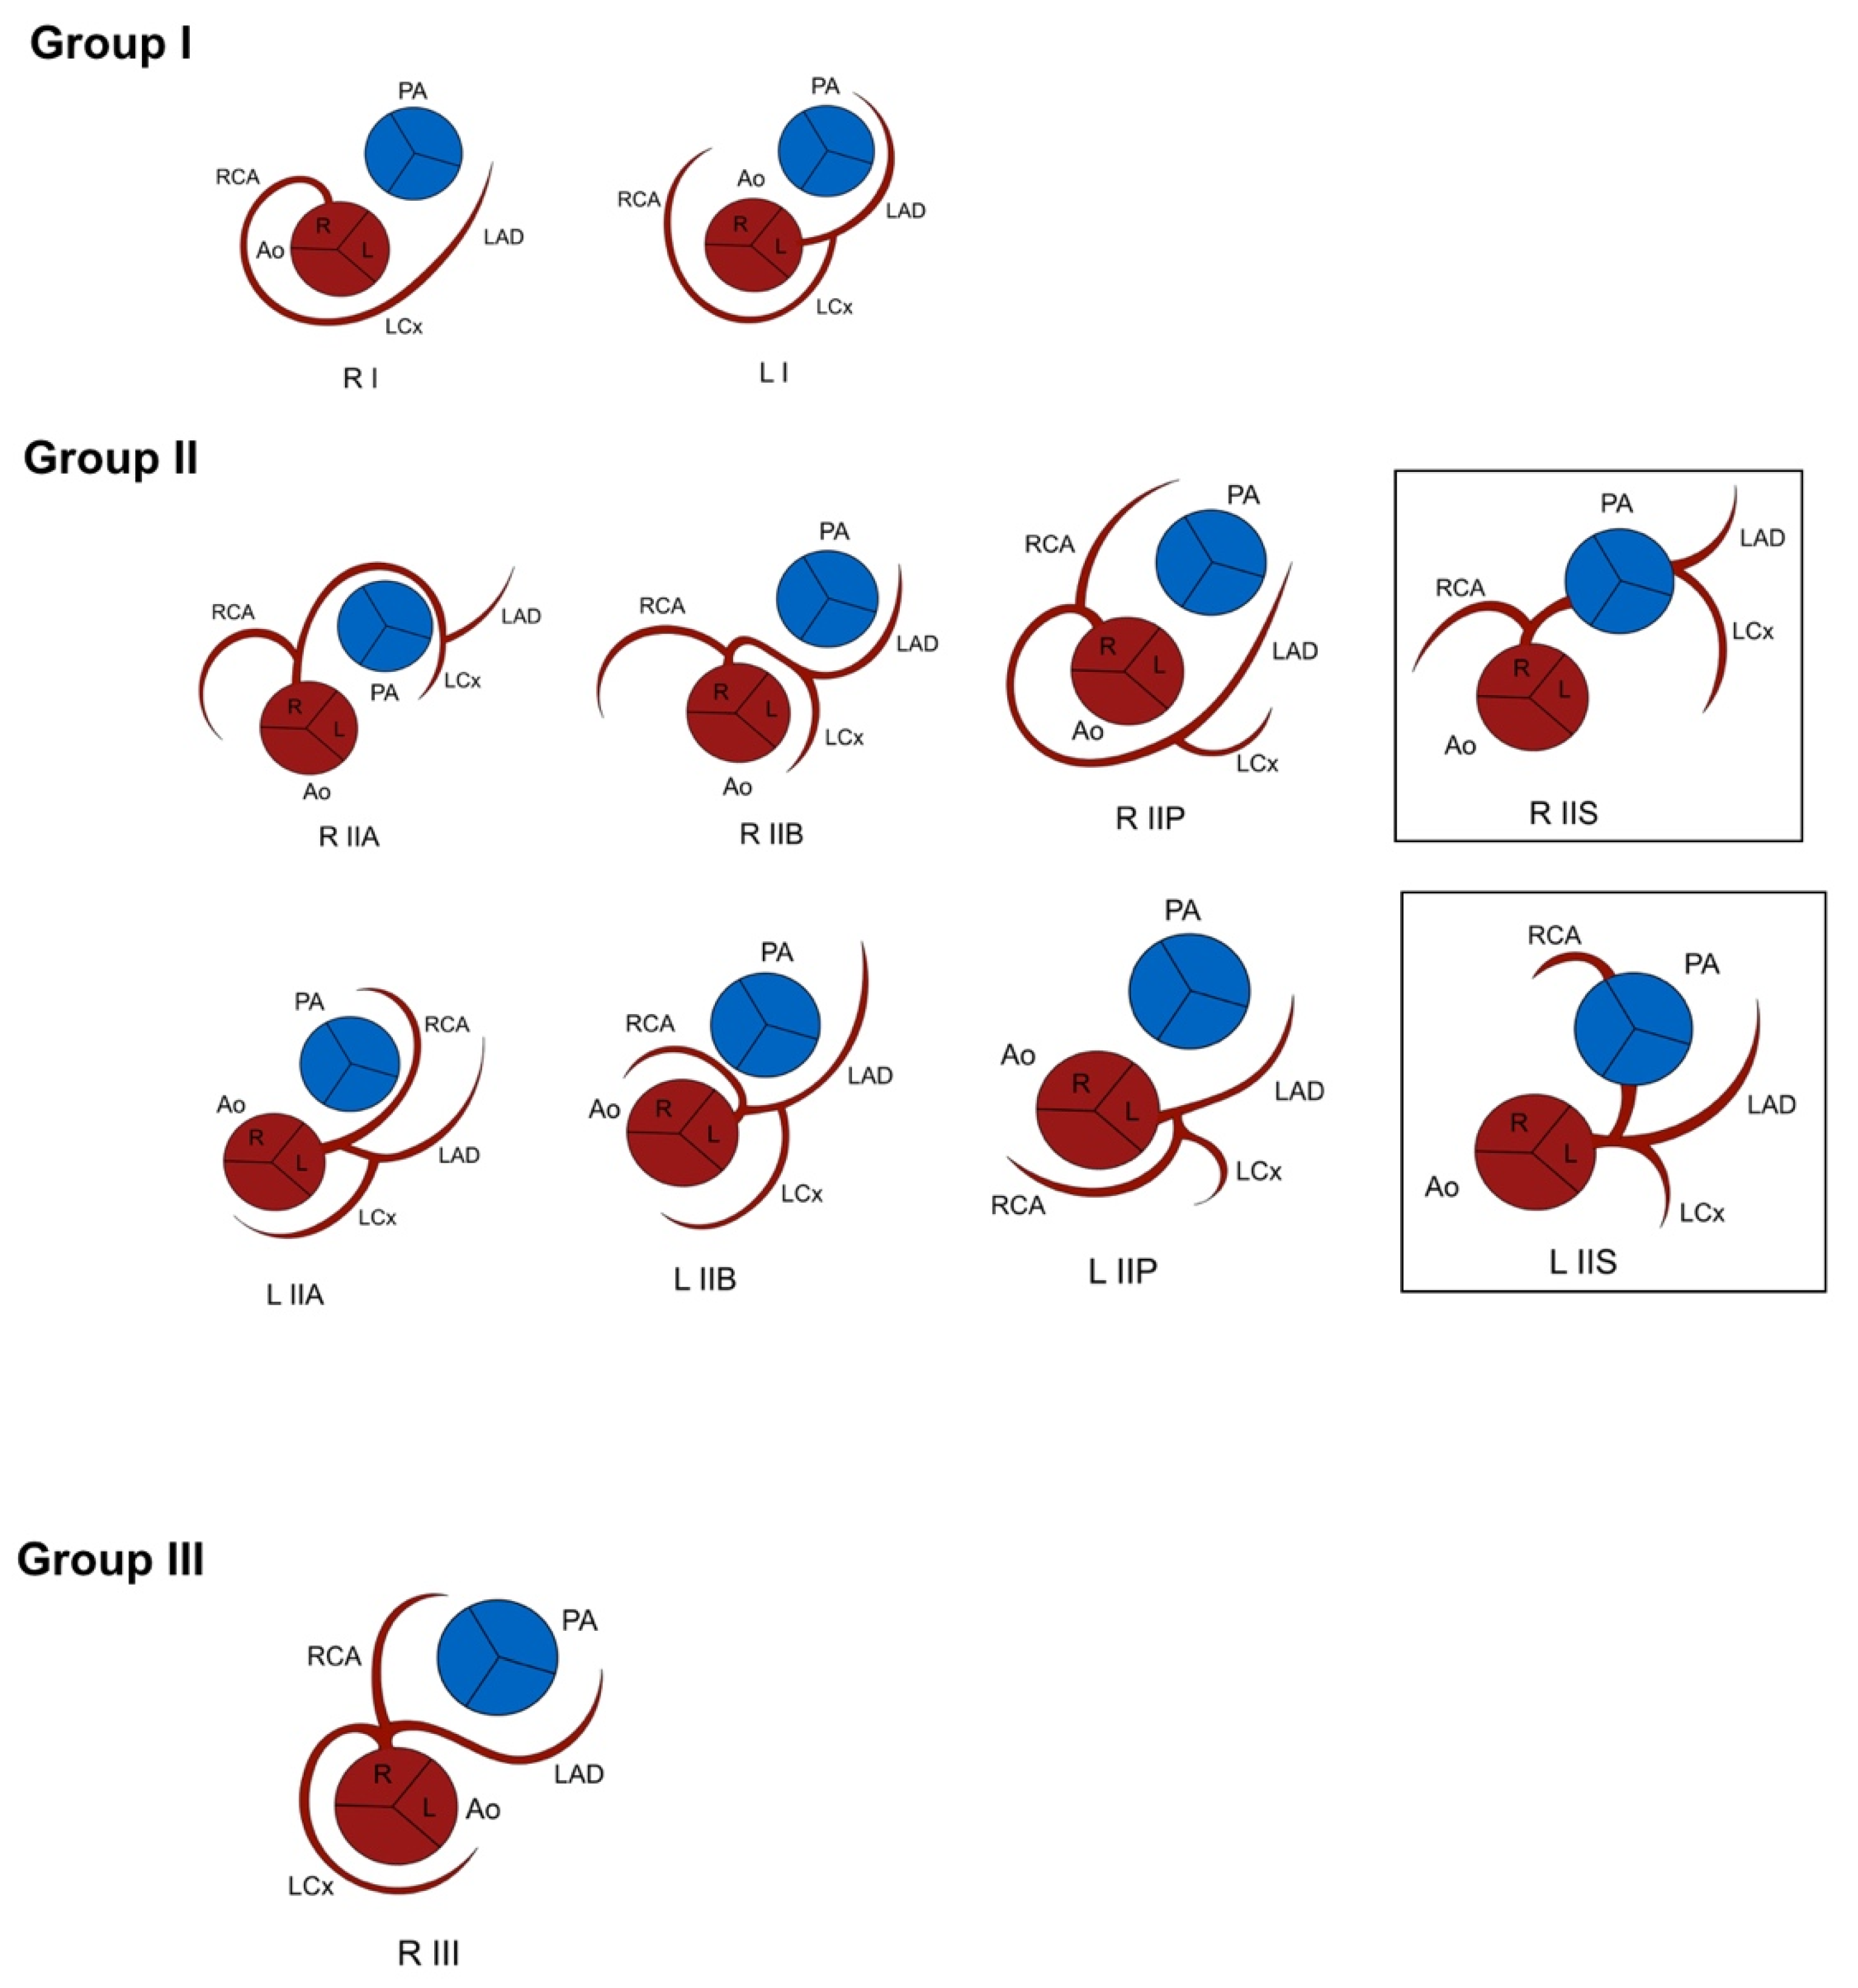

3.1. Lipton Classification